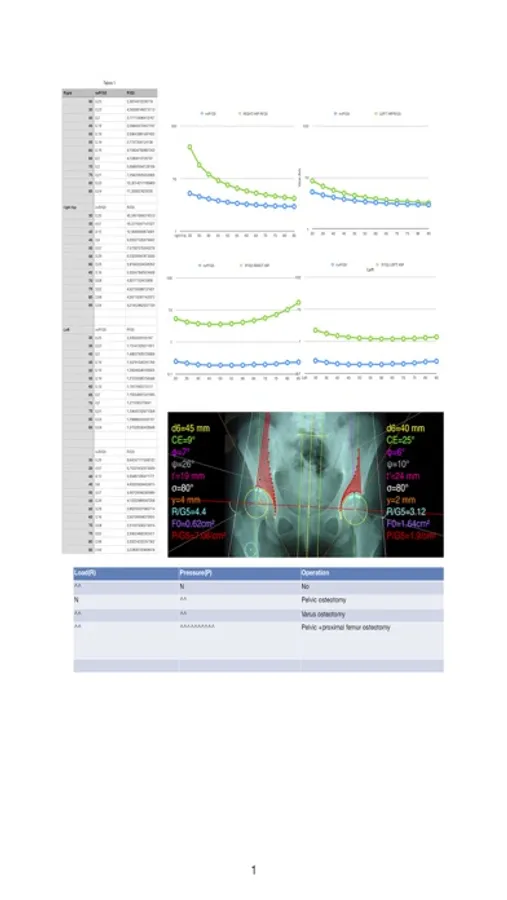

-By marking certain points in a simple standard AP pelvic radiograph, geometric parameters are being calculated. The App computes weight-bearing contact surface, the load (R) and stress (P) on the measured hip.

Data from load and pressure distribution in the hip - like in a real biomechanicals tests- are being measured and depicted graphically as vectors over the X-ray in the screen over the joint. The distribution also of compressive stresses over the acetabulum, which is usually associated radiographic sclerosis over the acetabular margin, are printed in real time over the screen and thus can be easily and objectively evaluated. Besides that, the App provides data in export for diagrams of load (R) pressure (P), which each can be plotted as a curve allowing easy comparison with normal data and thus help decide the orthopaedic surgeon which procedure is objectively indicated.

-The data are printed over to screen so each case can easily assessed

-Save the planned images, for later review or consultation. Data are exported as txt file, ready to print or to input as cells to numbers or excel ready for chart printing and further research.